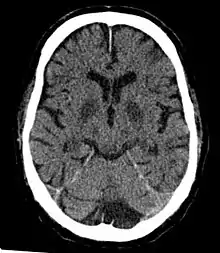

Classification

Cerebral hypoxia is part of four categories of brain's oxygen deprivation:[20]

- Diffuse cerebral hypoxia – A mild to moderate impairment of brain function due to low oxygen levels in the blood.

- Focal cerebral ischemia – A stroke occurring in a localized area that can either be acute or transient. This may be due to a variety of medical conditions such as an aneurysm that causes a hemorrhagic stroke, or an occlusion occurring in the affected blood vessels due to a thrombus (thrombotic stroke) or embolus (embolic stroke).[21] Focal cerebral ischemia constitutes a large majority of the clinical cases in stroke pathology with the infarct usually occurring in the middle cerebral artery (MCA).[22]

- Global cerebral ischemia – A complete stoppage of blood flow to the brain.

- Cerebral infarction – A "stroke", caused by complete oxygen deprivation due to an interference in cerebral blood flow which affects multiple areas of the brain.

Cerebral hypoxia can also be classified by the cause of the reduced brain oxygen:[23]

- Hypoxic hypoxia – Limited oxygen in the environment causes reduced brain function. Divers, aviators,[24] mountain climbers, and fire fighters are all at risk for this kind of cerebral hypoxia. The term also includes oxygen deprivation due to obstructions in the lungs. Choking, strangulation, the crushing of the windpipe all cause this sort of hypoxia. Severe asthmatics may also experience symptoms of hypoxic hypoxia.

- Hypemic hypoxia – Reduced brain function is caused by inadequate oxygen in the blood despite adequate environmental oxygen. Anemia and carbon monoxide poisoning are common causes of hypemic hypoxia.

- Ischemic hypoxia ( or "stagnant hypoxia") – Reduced brain oxygen is caused by inadequate blood flow to the brain. Stroke, shock, cardiac arrest and heart attack may cause stagnant hypoxia. Ischemic hypoxia can also be created by pressure on the brain. Cerebral edema, brain hemorrhages and hydrocephalus exert pressure on brain tissue and impede their absorption of oxygen.

- Histotoxic hypoxia – Oxygen is present in brain tissue but cannot be metabolized by the brain tissue. Cyanide poisoning is a well-known example.